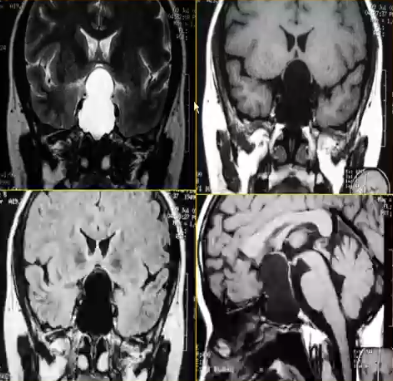

图例:女,37岁,视力下降2月,MRI发现垂体区囊性占位,手术为垂体囊肿。术后视交叉下移。

√垂体单纯囊肿为垂体少见病变,以垂体及邻近结构压迫产生症状

√CT、MRI表现:

1)垂体窝内的液体密度或信号

2)有囊壁结构,液体局限化

3)占位效应可与空蝶鞍鉴别